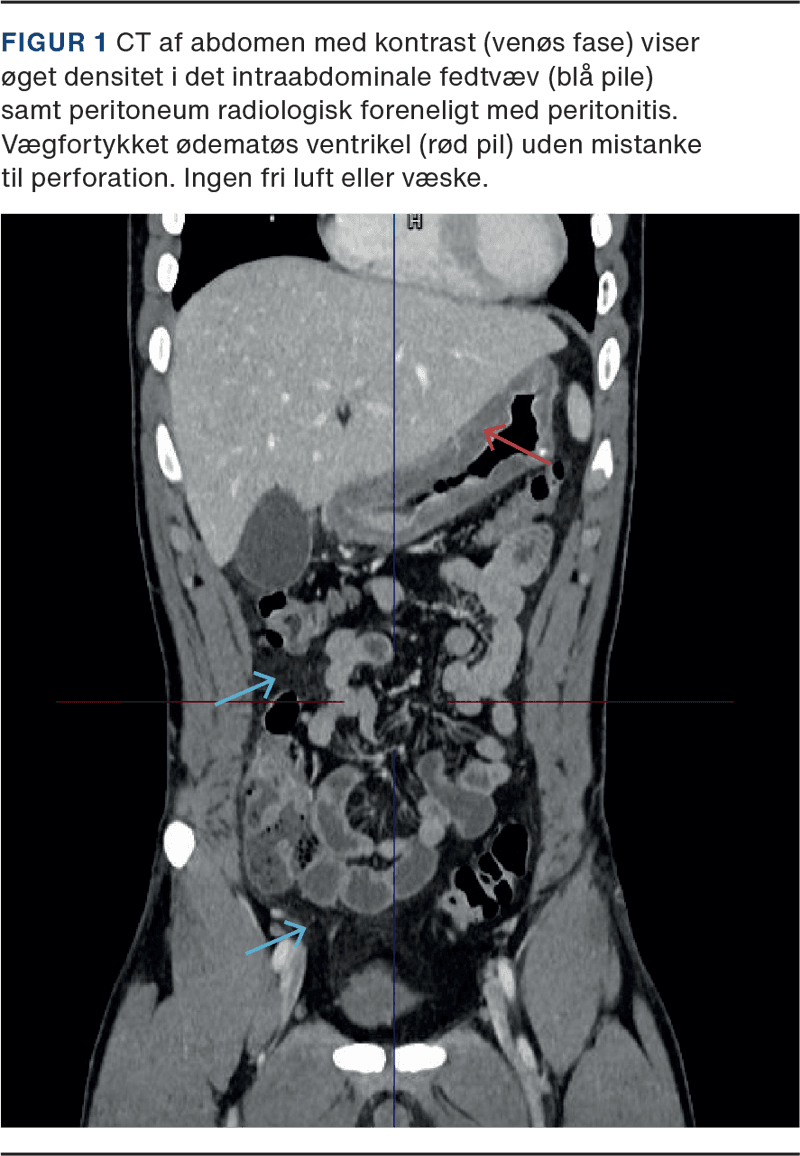

På baggrund af uafklaret akut abdomen med peritonealia blev akut højrisiko abdominalkirurgi (AHA)-forløb iværksat inkl. administration af piperacillin/tazobactam. CT af abdomen viste let fortykket ventrikelvæg og diffus peritonitis uden oplagt indgangsport (Figur 1).